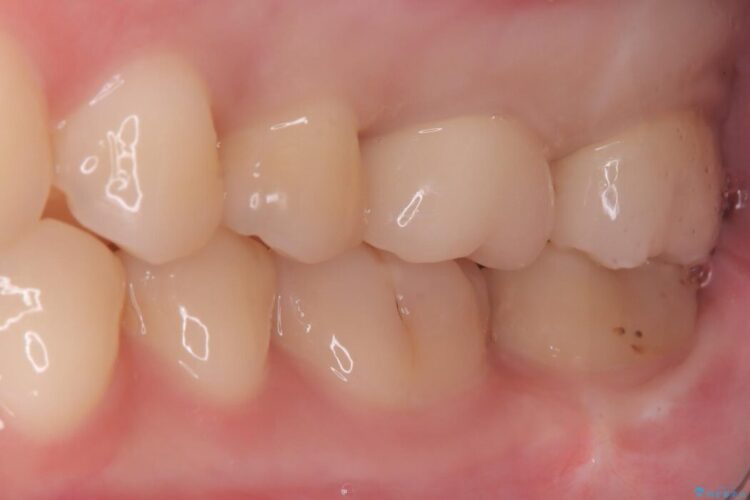

治療概要

- 患者様:20代女性

- 治療期間:2ヶ月

- 治療回数:2~5回

- 概算治療費:40万円

※費用は治療当時の料金となります - 担当医:河口智英

治療動機

「冷たいものが強くしみる」とご相談にいらした患者様です。

治療計画

精密検査の結果、非常に深い虫歯があり、通常であれば抜髄が必要な状態でした。

しかし、神経を抜くと歯の寿命が縮まってしまうため、今回は神経の一部を温存する部分的断髄法(VPT)を提案しました。

高い殺菌性と封鎖性、そして組織の再生を促す効果を持つMTAセメントを使用して神経を保護し、最終的には強度と審美性に優れたセラミックで修復する計画を立案しました。